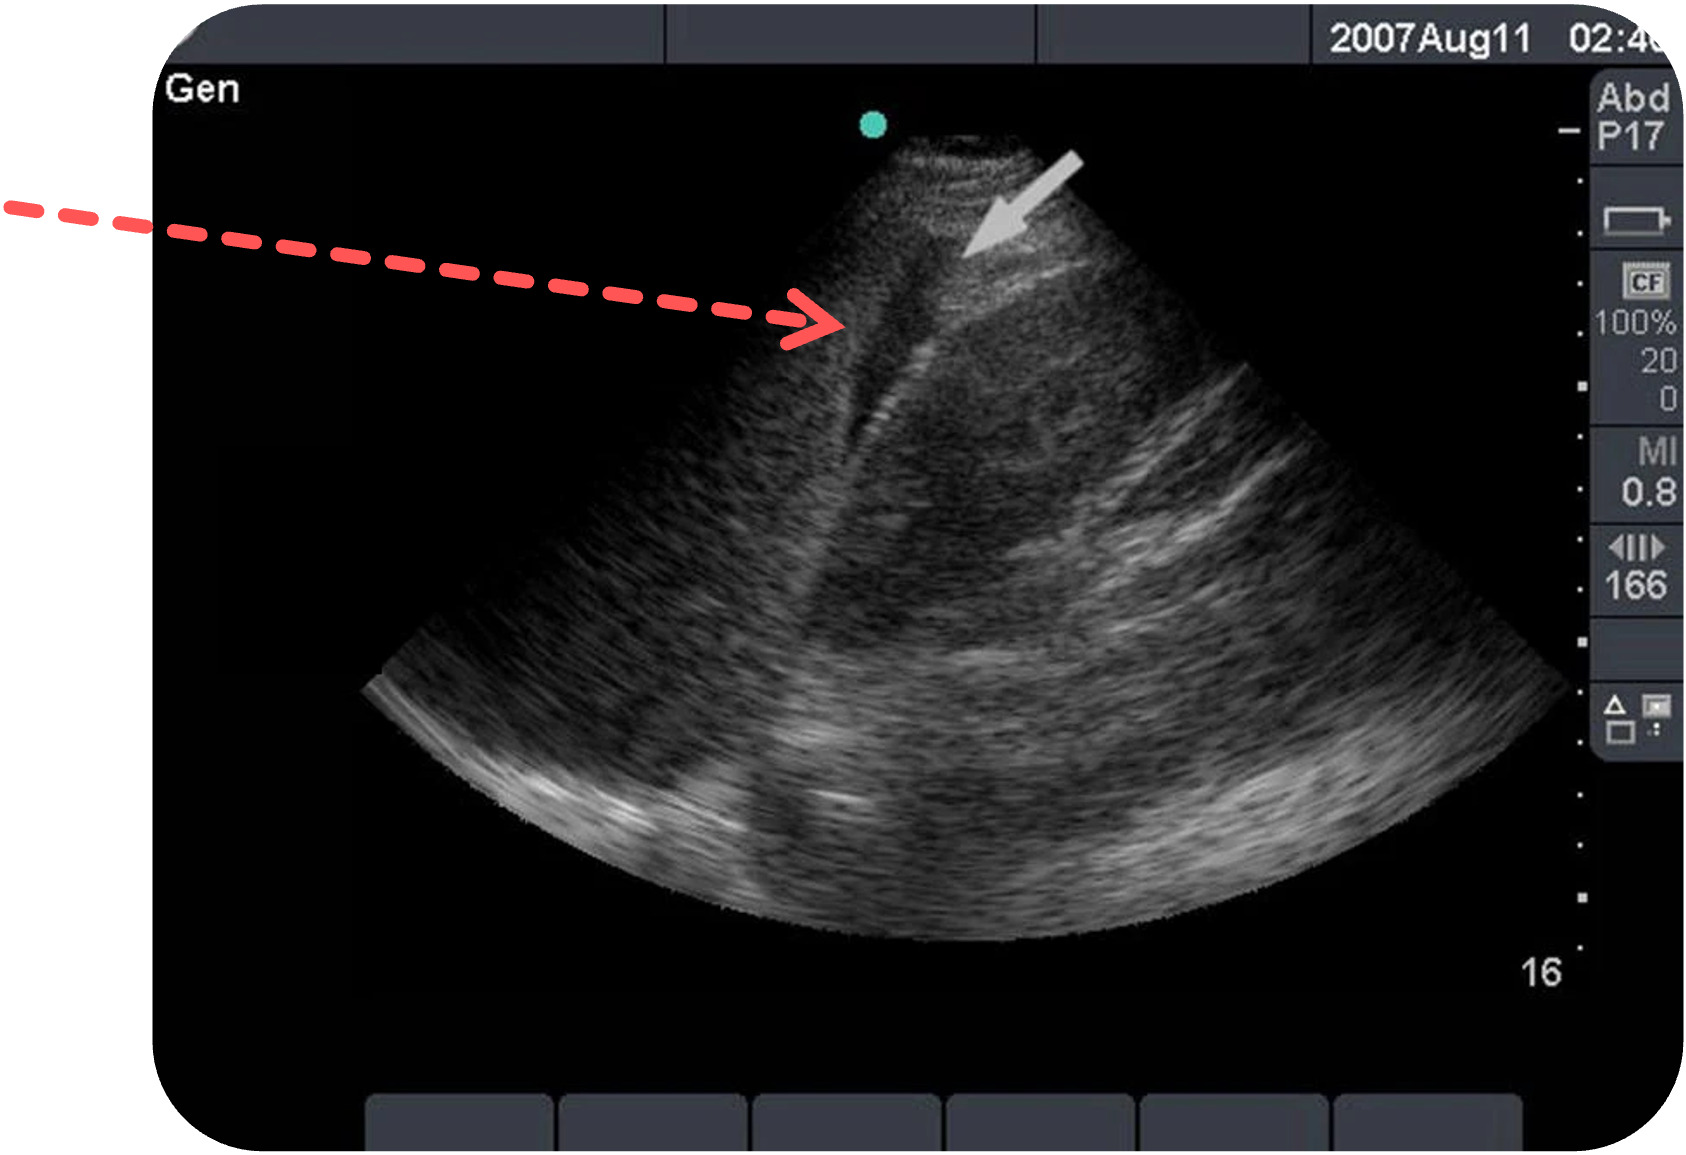

Typischer Befund:

Eine anechore, statische Flüssigkeitssichel zwischen Milz und Niere. (Siehe Pfeil)

Figure 8 aus Ketelaars, R., Reijnders, G., van Geffen, GJ. et al. ABCDE of prehospital ultrasonography: a narrative review. Crit Ultrasound J 10, 17 (2018). https://doi.org/10.1186/s13089-018-0099-y. Es wurde der rote Pfeil ergänzt.